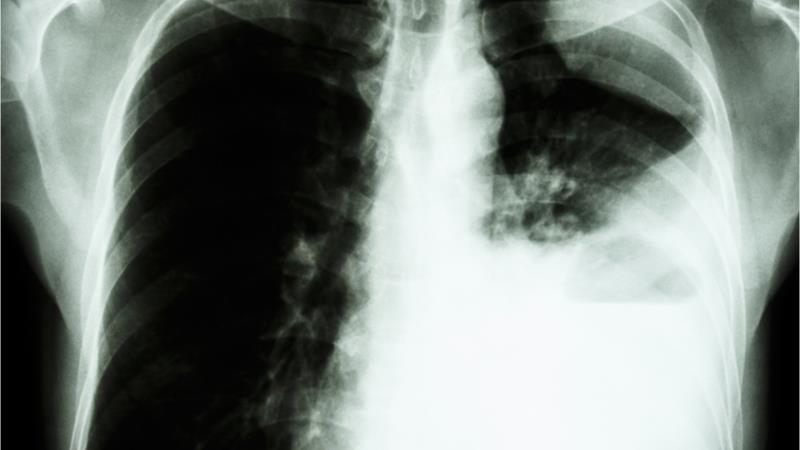

Dacomitinib monotherapy approved as first-line treatment for metastatic NSCLC

The National Pharmaceutical Regulatory Agency (NPRA) has approved dacomitinib (VIZIMPRO®, Pfizer) as a monotherapy for the first-line treatment of adult patients with metastatic non-small cell lung cancer (NSCLC) with epidermal growth factor receptor (EGFR)-activating mutations.